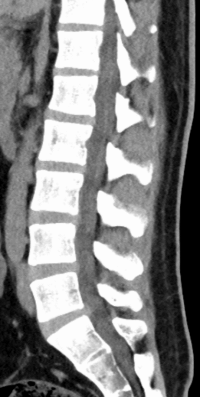

2.CT扫描:

优势:对骨性结构显示清晰,能准确判断骨折.骨质增生.椎管狭窄等病变,也可粗略观察椎间盘形态和钙化情况。

局限:对软组织分辨率低于MRI,辐射剂量高于X线。

适用情况:外伤后怀疑骨折.骨质疏松性压缩骨折.骨刺或钙化检测,以及术前评估骨性结构病变。